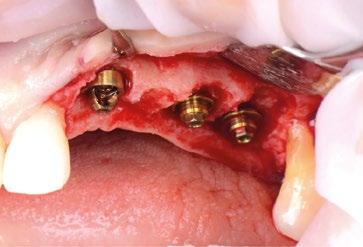

Limitaciones de los pilares Multi-unit clásicos en la zona transgingival

La importancia en la preservación del hueso crestal alrededor de los implantes y de las distintas estructuras del fenotipo periimplantario es vital para el mantenimiento y éxito funcional y estético a largo plazo (Ref.2). La utilización de conexiones cónicas robustas, mecánicamente estables y con cambio de plataforma como las de NobelActive® y NobelParallel™ pueden ayudar al mantenimiento del hueso crestal (Ref.3). Sin embargo, también es importante asociar este tipo de conexiones con la posición tridimensional del implante (Ref.4). Concretamente en el plano apico-coronal, la colocación de los implantes en posiciones subcrestales va a ayudar no solo a mantener el hueso, sino que va a permitir generar el espacio necesario para establecer una zona de transición biológica y protésicamente necesaria para desarrollar los perfiles de emergencia adecuados hasta llegar a la anatomía del margen gingival de la corona o perfil crítico (Ref. 5). Según las publicaciones, este espacio está establecido 3,5-4mm del margen gingival (Ref.6, Ref.7). Desde el punto de vista restaurador en implantes unitarios, es conocido que estos perfiles de emergencia deben ser diseñados con una transición suave. Partiendo desde un diámetro estrecho que progresivamente se va ensanchando. Siempre que el implante esté bien colocado tridimensionalmente el resultado será un perfil de emergencia cóncavo en el área subgingival. (Refs.8,9,10). La finalidad del concepto es proporcionar el máximo espacio horizontal para el crecimiento de tejido conectivo supracrestal alrededor de la interfase de titanio o pilar personalizado ofreciendo protección al implante a costa de maximizar el grosor y estabilidad a las estructuras del fenotipo periimplantario (Ref.11).

El verdadero reto surge en situaciones en las que es posible crear una prótesis múltiple del tipo FP1 (Ref.12), donde siempre se debe utilizar un pilar Multi-unit. Cuando se utiliza un implante asociado a este tipo de pilar para crear una emergencia natural desde la encía, éste se debe planificar teniendo en

cuenta que el volumen del pilar va a ocupar prácticamente toda el área de la altura de tejido supracrestal (“Suprecrestal tissue height” Ref. 11) y debe estar “camuflado” en dicha zona de transición ocupando gran parte del espacio para el tejido conectivo supracrestal y del perfil de emergencia de la restauración (Ref. 13). Ya sea un pilar recto o angulado, debido a sus formas robustas y perfiles anchos, resulta difícil de planificar su colocación en zonas estéticas ya que el complejo implante-pilar se va a comportar como un implante tipo “tissue level” (Ref.14)

(Fig.1). Con los diseños clásicos de pilares no se van a poder respetar las concavidades subgingivales deseadas y siempre va a implicar la eliminación de hueso, sobre todo a nivel interproximal y vestibular en la zona del cenit del diente (Ref.15) (Fig.2). Las consecuencias automáticas serán picos de hueso interproximales reducidos, papilas más cortas y dientes con cenits más planos y anchos en el tercio gingival. Incluso en situaciones de implantes adyacentes puede provocar la pérdida o ausencia total de papila interimplantaria (Ref.7) (Fig.3).

Innovaciones y características del nuevo pilar Multi-unit: perfiles para preservar Debido a esta compleja situación, se ha desarrollado una nueva línea de pilares Multi-unit que rompe con los diseños clásicos y que se presenta a continuación: (Figs. 4,5).

Con respecto al Multi-unit recto, su principal característica es la emergencia desde la plataforma del implante con un perfil completamente cóncavo. Por una parte, va a maximizar el efecto de “cambio de plataforma” en su parte más crestal a nivel de la plataforma del implante y por otra va a facilitar mucho más espacio para la creación de tejido conectivo supracrestal a lo largo de toda la transición hasta la plataforma restauradora. El perfil cóncavo del pilar también respetará en mayor medida los espacios comprendidos entre el pilar y el hueso interproximal (en el caso de una colocación subcrestal entre 1,5 y 2mm) para poder preservar al máximo las estructuras anatómicas presentes que soportarán las papilas periimplantarias.

Así como el diseño clásico de pilar hacía prácticamente imposible la colocación de implantes inmediatos en zona estética, el nuevo perfil cóncavo del pilar Multi-unit hace que se convierta en un pilar ideal para estas situaciones. La altura de pilar de 3 ,5 mm, hace que se pueda colocar la plataforma del implante en la posición corono-apical deseada con respecto al margen gingival sin involucrar el hueso adyacente y permitiendo desarrollar un mínimo perfil de emergencia restaurador más horizontal para soportar cenit y tejido interproximal. (Fig.6-7) Otra característica de diseño importante es la reducción del bisel de la plataforma res-

tauradora tanto en los pilares rectos como en los pilares angulados. Sin cambiar su diámetro clásico de 4,8mm ni su compatibilidad para atornillar y asentar cualquier aditamento restaurador de toda la gama Multi-unit, el nuevo pilar presenta una plataforma mucho más fina y estilizada que facilitará también su inserción incluso sin necesidad de utilizar la fresa “bone mill” o molinillo de hueso. De esta manera no solo se seguirá incrementando la preservación ósea, sino que también se reducirán los tiempos quirúrgicos al evitar tener que atornillar y desatornillar la guía del molinillo o “Bone Mill Guide”. (Figs. 8-12)

La colocación del implante inclinado de 30º siempre implica que la zona más mesial de la plataforma se encuentra en posición yuxtaósea y la zona distal en posición subcrestal. Clásicamente se debe utilizar el instrumento “bone mill” de 5,2mm (NP) o 6,2mm (RP) para poder insertar el pilar en la posición deseada. En la figura 14 (Fig.14) se observa una situación clínica comparativa donde se han colocado implantes inclinados con una orientación de 30º aproximadamente en dirección hacia los rebordes piriformes en una premaxila. Claramente se puede observar la cantidad de remodelación ósea provocada por el molinillo versus la preservación que ofrece la colocación el nuevo Multi-unit sin necesidad de acondicionar la cresta ósea. En configuraciones de tipo All-on-4®, en los implantes distales se produce una situación similar. El inconveniente que se puede producir en estos casos es la posibilidad de la aparición de una recesión de la mucosa periimplantaria alrededor del pilar precisamente por la combinación de quedar la zona sin soporte óseo y por el propio volumen excesivo que ocupa el pilar. Por el contrario, mediante la utilización de los nuevos perfiles no existe necesidad de remodelar el reborde alveolar y conjuntamente al menor volumen que ocupan los pilares, el tejido (si es suficiente) será capaz de mantenerse en mayor medida. En las figuras 15 a 18 (Fig.15-18) se describe una situación común donde se utiliza el pilar Multi-unit de 17º. En pacientes edéntulos o futuramente edéntulos en la zona de la premaxila. Para maximizar el hueso disponible en esta